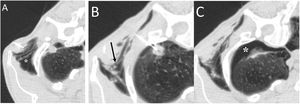

A 58-year-old man with fever and dysphagia. A and B) The computed tomography showed an oesophageal wall thickening (white asterisk) and a fistulous path between the oesophagus and the intrathoracic trachea, clearly visualised when oral contrast was administered (white arrows). C) In the pulmonary parenchyma window, pulmonary consolidation was visualised in the right upper lobe (black asterisks). The radiological findings indicated an oesophageal neoplasm with tracheo-oesophageal fistula and aspiration pneumonia in the right lung. The patient was treated by placing an oesophageal endoprosthesis, with significant clinical improvement.

A 48-year-old man with lung neoplasia treated with surgery and chemotherapy. A and B) The computed tomography (CT) scan showed the presence of a subcarinal adenopathy (black asterisk) that in the next control CT scan necrotised and filled with air (white asterisk). In addition, a right lower lobe lung consolidation was seen due to aspiration pneumonia (white asterisks). C) MinIP reconstruction (coronal plane) revealed a fistula between the intermediate bronchus (black arrow) and the necrotic adenopathy (white arrows).